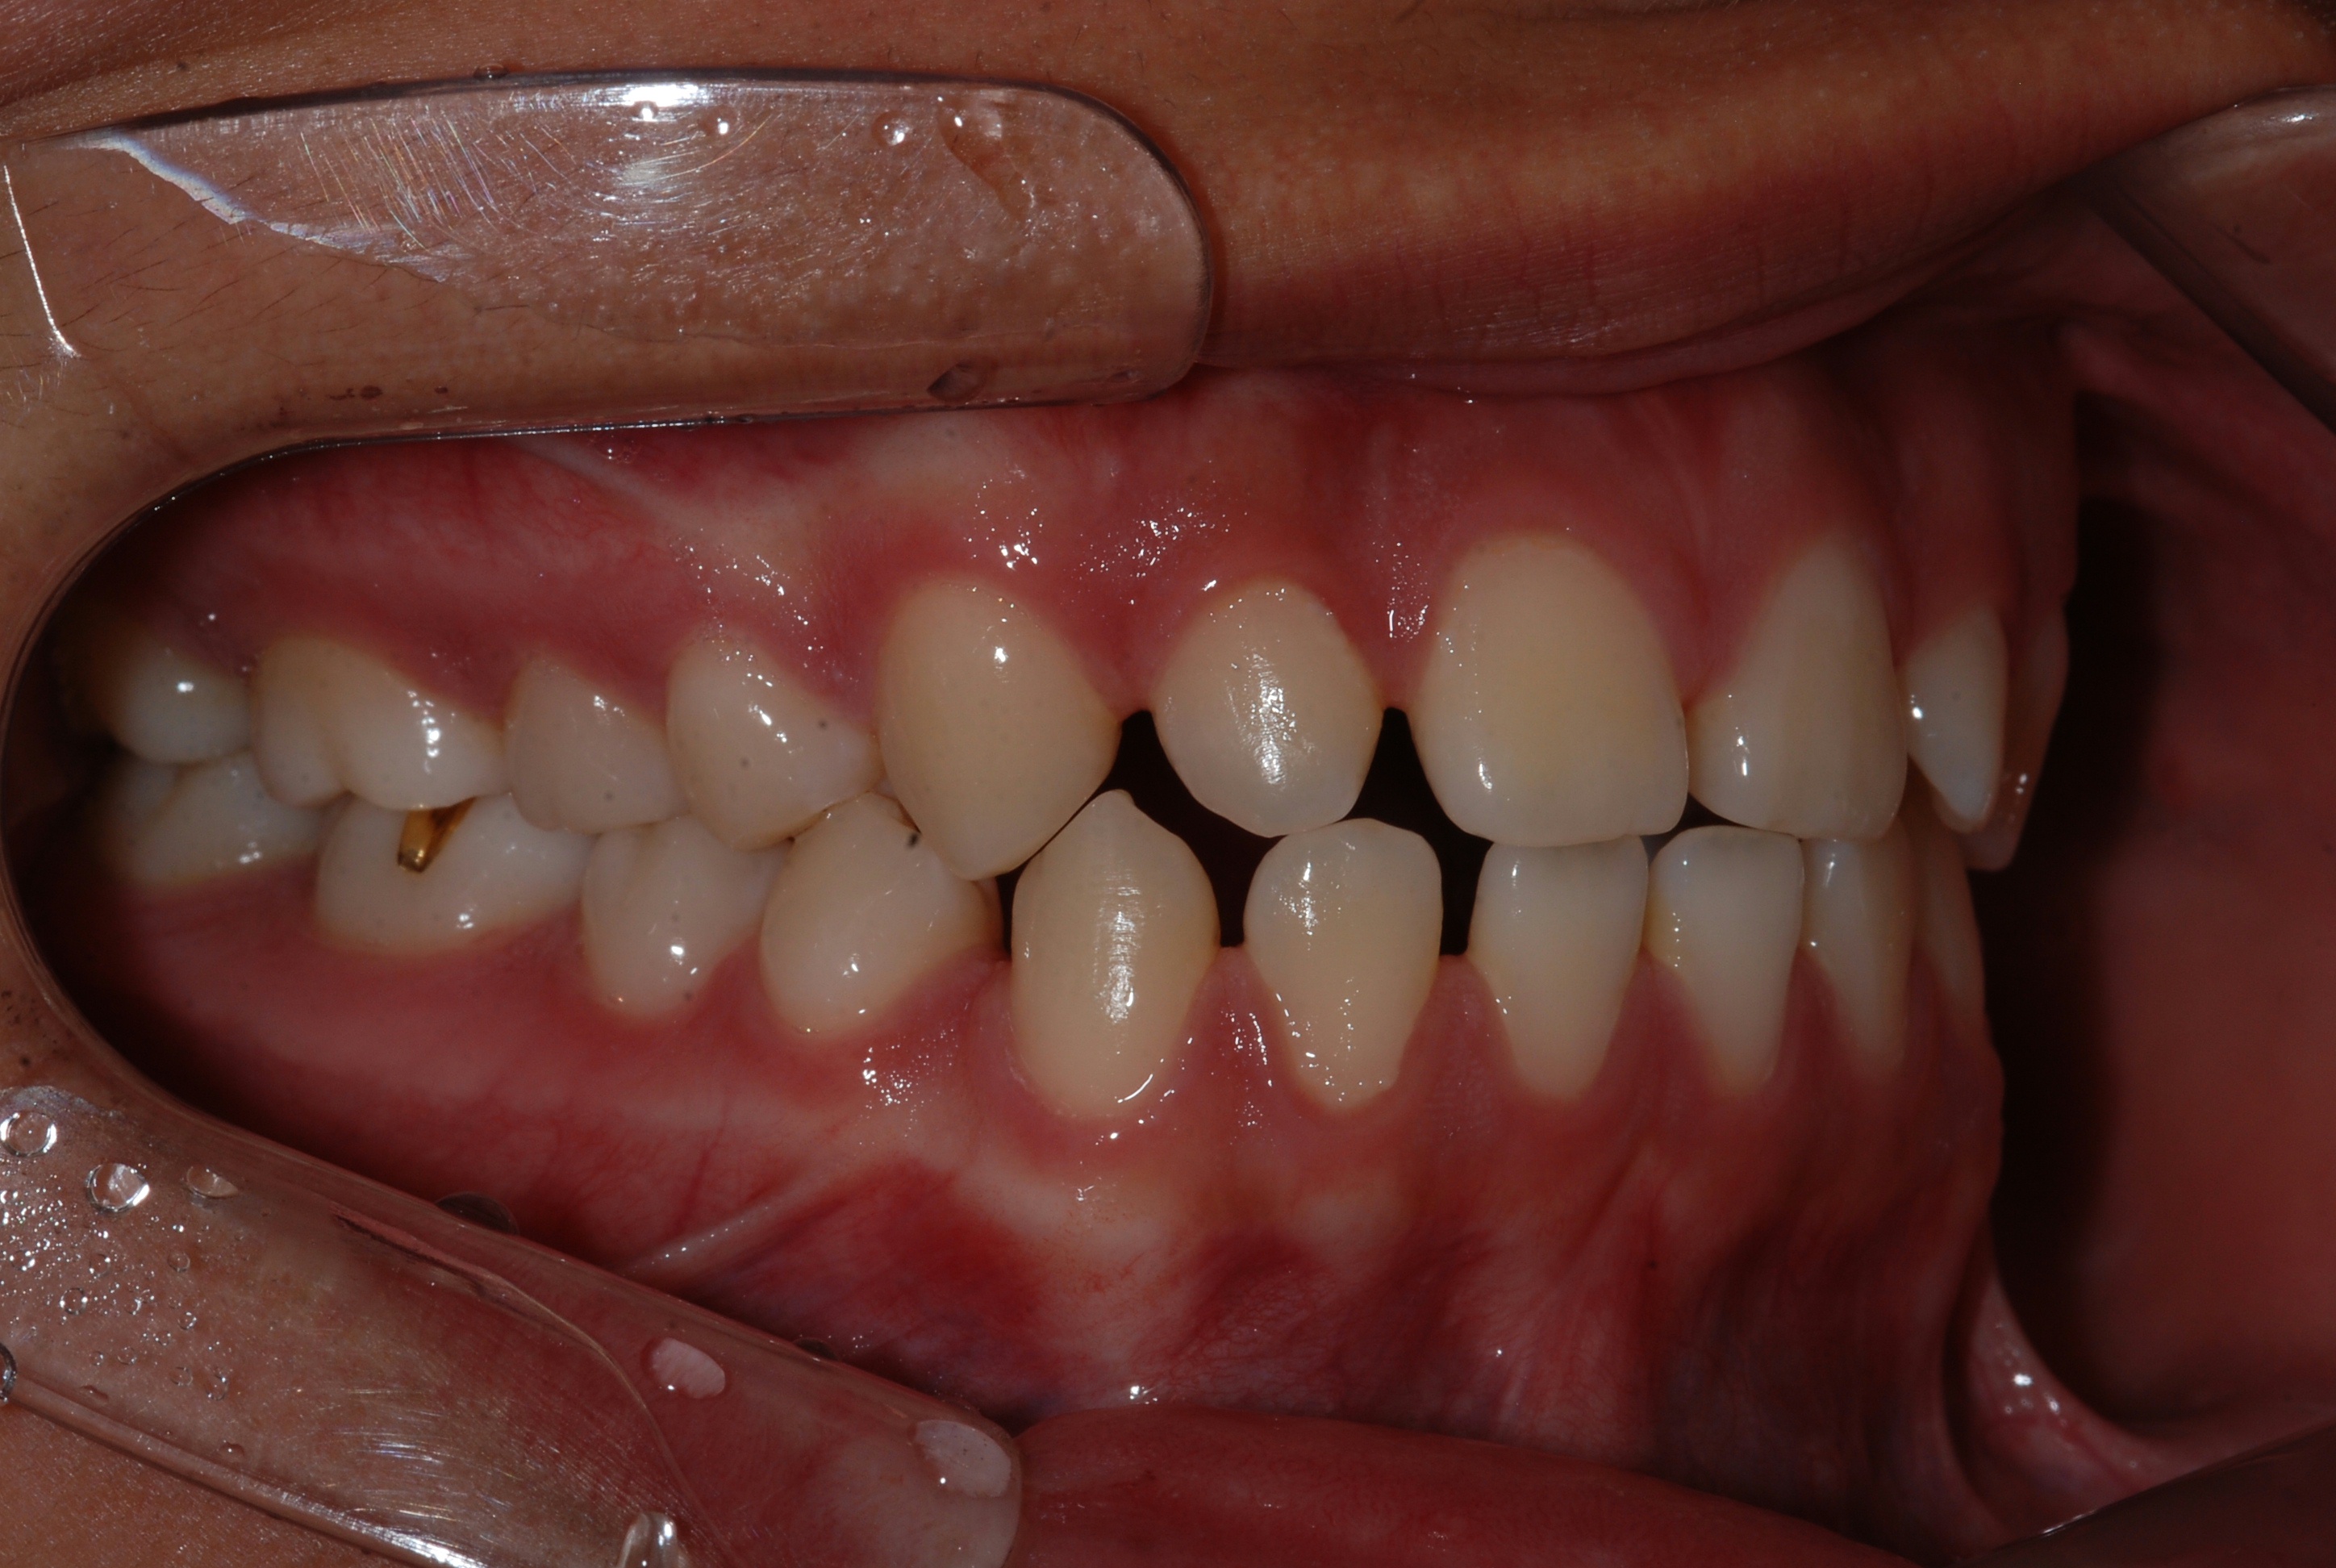

치료 후 사진입니다.